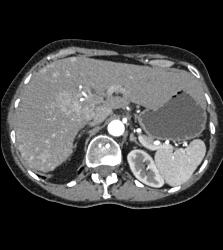

Hepatocellular Carcinoma (Hepatoma) - See All Phases of This Tumor